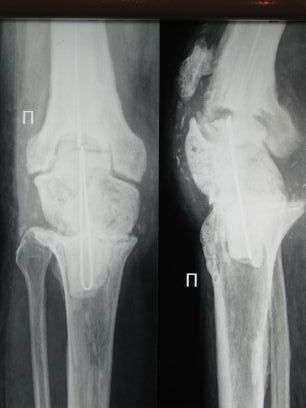

Пациент 69 лет.С 2002 года пережил три эндопротеза правого коленного сустава. В ноябре 2008 года эндопротез удален, дефект заполнен спейсером. В ноябре же был эпизод воспаления в области надколенника.

Задача на момент поступления - создать опорную ногу за короткий промежуток времени.

Блокируемый штифт, проведенный сквозь спейсер?

Извиняюсь, не сразу увидел снимок. Хотя академически возможность имплантации эндопротеза (при отсутствии инфекции) существует.

Я думаю, аппарат Илизарова - артродез с коррекцией длины (или с коррекцией обувью, решать вам и пациенту).

не удивляясь, что пациенту дважды выполненялось ревизионное эндопротезирование,хочется сказать, что другого пути кроме артродеза в в АВФ у Вас и у пациента нет. На данный момент времени.

О каком штифте на фоне свищей может идти речь?????? Да еще с не удаленным спейсером!!!!

Имеются прямые показания для артродеза коленного сустава.

Если инфекционный процесс еще не прекратился, то правильней делать артродез

аппаратом наружной фиксации.

Конечно нога будет короче, но за то опорная и без боли.